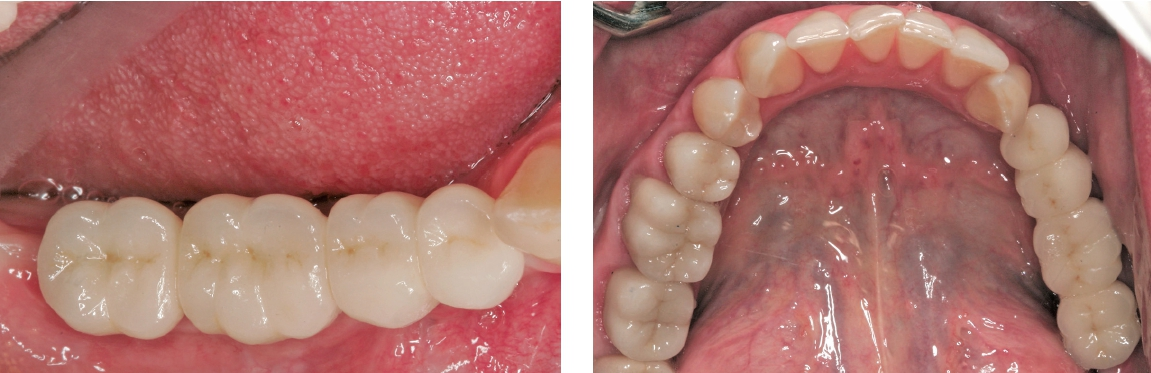

Nach der erfolgreichen Eingliederung der Prothetikkomponenten wurde die keramikverblendete Brücke aus Zirkondioxid mit einem Glasionomerzement auf den Sekundärteilen befestigt (Abb. 27 und 28).

Eine abschließende Röntgenaufnahme zeigte die perfekte Passung der prothetischen Arbeit (Abb. 29).